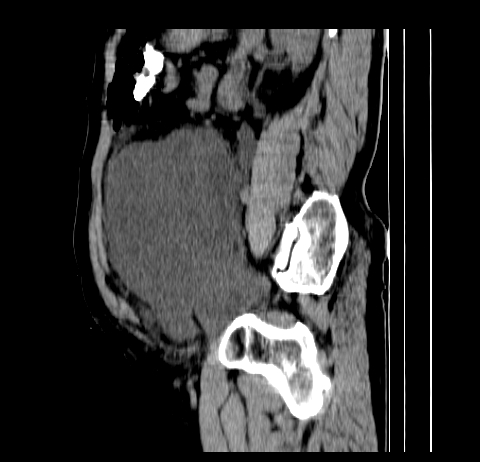

标题: CT19729B:男,74岁,因腿疼就诊,查体触腹部肿物,

增强扫描

延时期

重建

【ct表现】

1、肿块巨大,往往位于腹膜后,长大后才引起症状而就诊;那么位于腹膜后的肿瘤80%为恶性肿瘤。

2、实性肿瘤,增强扫描轻度不均强化,实性肿瘤一般不是好东西。

3、肿瘤边缘似见少许脂肪样密度。

4、腹膜后未见肿大淋巴结,但肿瘤于临近的肠管及组织接触紧密。

腹部占位,考虑位于腹膜后的恶性肿瘤,脂肪肉瘤(实体型)可能性大。

术后病理结果:腹膜后脂肪肉瘤。